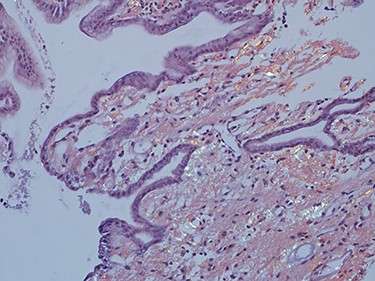

As work up for his abdominal pain and anemia he underwent gastroscopy on 29 October 2020 that revealed congested and nodular gastric mucosa (mass-like) and at lesser extend in the first and second part of duodenum (Figs 1 and 2). Biopsies were taken from the gastric lesion and duodenum. Histopathological findings from gastric mass and duodenum showed marked stromal hyalinosis, which appeared as a cellular pink material on H&E stain (Figs 3 and 5). Congo red stain (amyloid stain) showed apple green birefringence under polarized light on both gastric and duodenal biopsies (Figs 4 and 6).

High power of duodenal biopsy showing stromal hyalinosis (H&E x 20).

Amyloid stain (Congo red) on duodenal biopsy showing the classic apple green birefringence under polarized light.